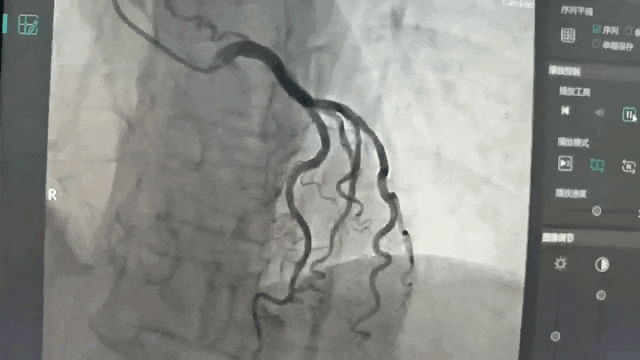

整体诊疗水平再上新台阶┃泸州福欣医院成功开展2例心脏介入手术

近日,泸州福欣医院成功开展2例心脏介入手术,标志着我院整体诊疗水平再上一个新台阶!为开展该类手术,医院一是引进原西南医科大学附属医院放射介入科胡高云医师担任学科带头人;二是安排专人到郑州附院,华西医院,西南医院,西南医科大附属医院进修学习;...